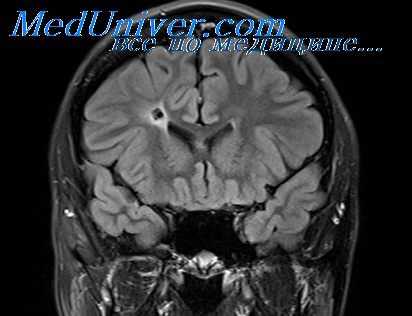

В последние годы для окончательного уточнения диагноза проводится компьютерная томография, хотя она еще далеко не везде доступна. Этот метод позволяет точно определить локализацию абсцесса, его размеры, глубину расположения, перифокальный отек мозговой ткани, перивентрикулярный отек.